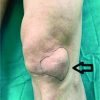

Arthroscopic resection of the right knee lesion was performed using the anterolateral and anteromedial portals. A yellow-brown mass was found in the anterior compartment; this mass had an irregular surface and was continuous to the infrapatellar fat pad (Fig. 3). The continuous part was cut and removed in one piece, and total synovectomy was performed after the removal of the mass. The removed specimen was tested for pathology. The patient was allowed to lead a normal life from the day after the surgery.